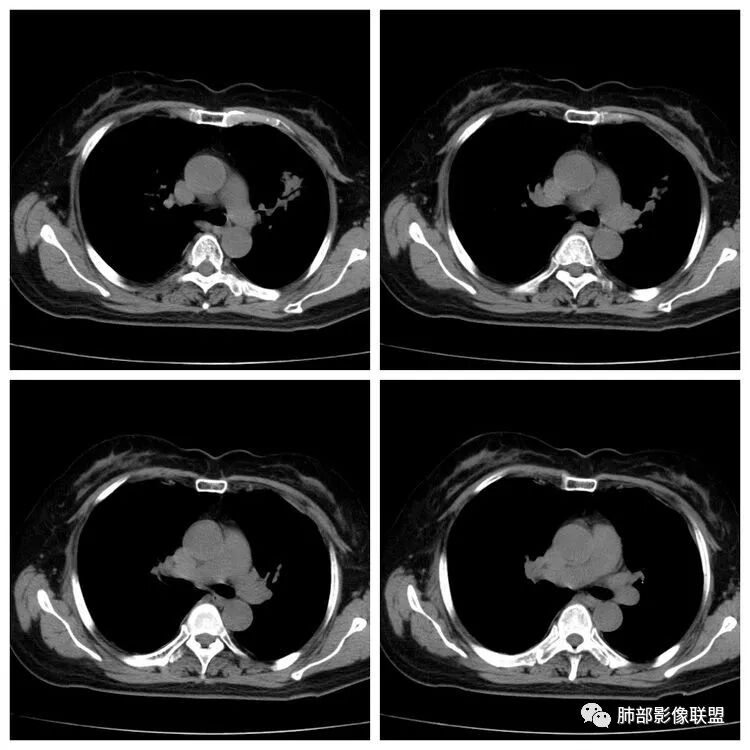

以下是两个时间点左右对比

2019.11.26  👇                           2020.01.20👇                                            2019.11.26片

2020.01.20片

2.早期CT表现左肺上叶不规则团块影,呈混合密度,以实性密度为主,但整体密度偏低,周围隐约见磨玻璃密度影。

边缘不规则,前内侧缘见小叶间隔限制(注意,并非典型深分叶),病灶外侧细长毛刺,病灶内有小空泡及空气支气管征,有胸膜牵拉征象。

上述征象均提示病灶为恶性病灶,但边缘特征及空气支气管征似乎有别于常见的浸润性腺癌及MALT。